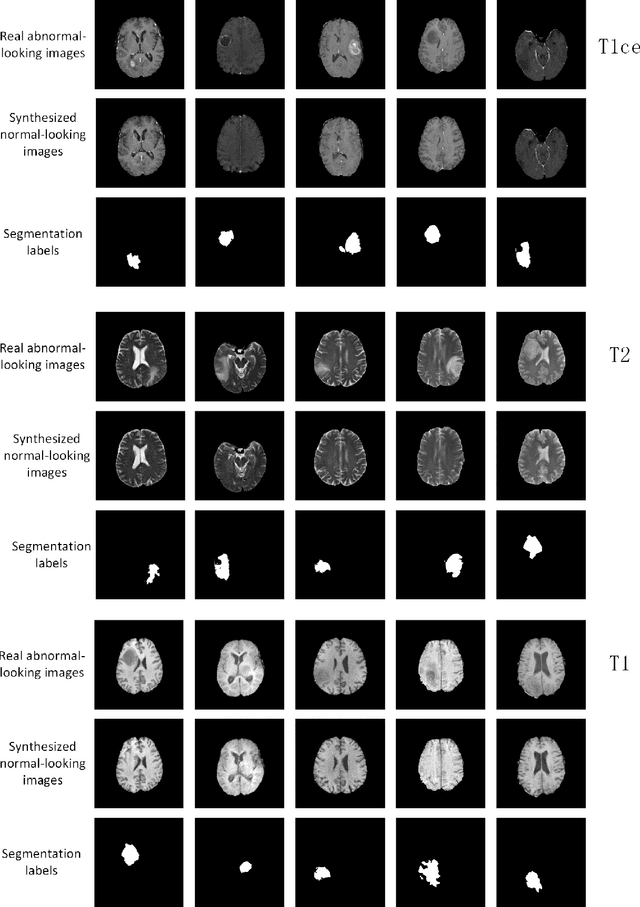

Abstract:The analysis of lesion within medical image data is desirable for efficient disease diagnosis, treatment and prognosis. The common lesion analysis tasks like segmentation and classification are mainly based on supervised learning with well-paired image-level or voxel-level labels. However, labeling the lesion in medical images is laborious requiring highly specialized knowledge. Inspired by the fact that radiologists make diagnoses based on expert knowledge on "healthiness" and "unhealthiness" developed from extensive experience, we propose an medical image synthesis model named abnormal-to-normal translation generative adversarial network (ANT-GAN) to predict a normal-looking medical image based on its abnormal-looking counterpart without the need of paired data for training. Unlike typical GANs, whose aim is to generate realistic samples with variations, our more restrictive model aims at producing the underlying normal-looking image corresponding to an image containing lesions, and thus requires a specialized design. With an ability to segment normal from abnormal tissue, our model is able to generate a highly realistic lesion-free medical image based on its true lesion-containing counterpart. Being able to provide a "normal" version of a medical image (possibly the same image if there is no illness) is not only an intriguing topic, but also can serve as a pre-processing and provide useful side information for medical imaging tasks like lesion segmentation or classification validated by our experiments.